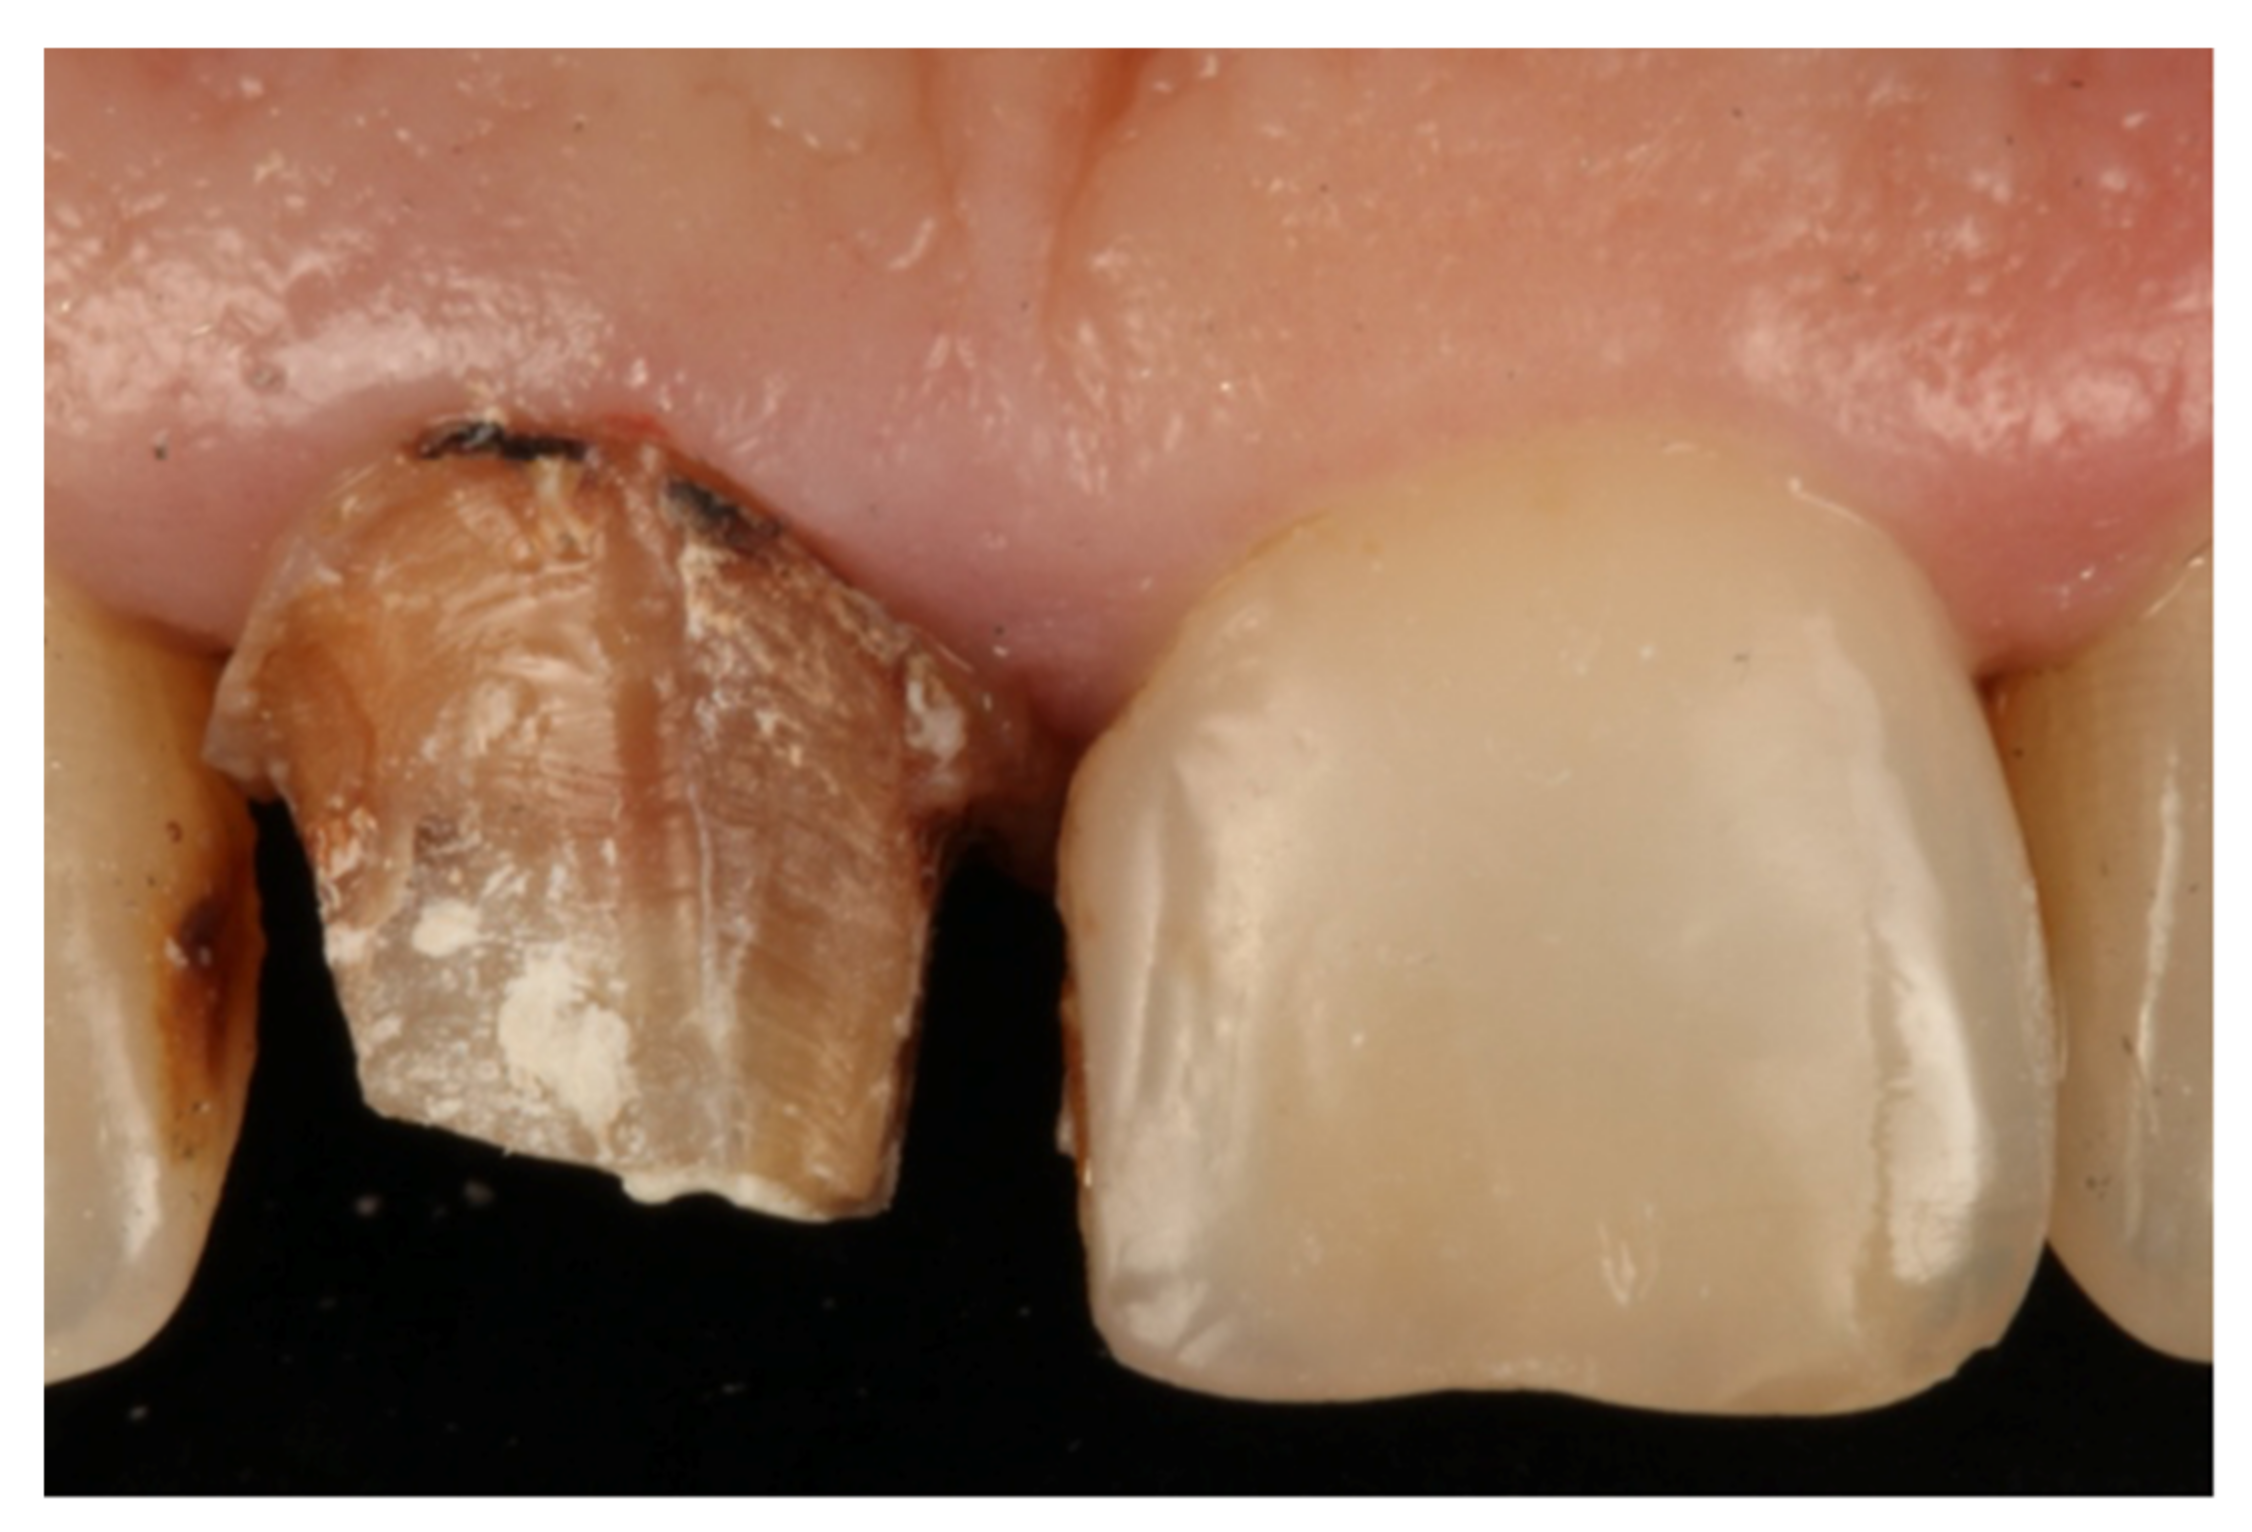

- Agustín-Panadero, R.; Solá-Ruíz, M.F. Vertical preparation for fixed prosthesis rehabilitation in the anterior sector. J. Prosthet. Dent. 2015, 114, 474–478. [Google Scholar] [CrossRef] [PubMed]

- Agustín-Panadero, R.; Serra-Pastor, B.; Fons-Font, A.; Solá-Ruíz, M.F. Prospective Clinical Study of Zirconia Full-coverage Restorations on Teeth Prepared with Biologically Oriented Preparation Technique on Gingival Health: Results After Two-year Follow-up. Oper. Dent. 2018, 43, 482–487. [Google Scholar] [CrossRef] [PubMed]